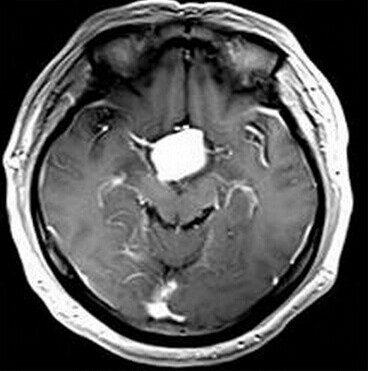

第三脑室脊索样胶质瘤

患者:男,50岁,记忆力下降1月余,双眼视力下降,反应减慢。

【正确答案】D 胶质瘤(第三脑室脊索样胶质瘤)

第三脑室脊索样胶质瘤的特征性表现是:

(1)见于成人,边界清楚,位于第三脑室前部;

(2)T1WI上为低信号,T2WI上呈明显高信号;

(3)增强后明显强化;

(4)肿块累及视交叉及下丘脑,但不浸润周围脑实质。